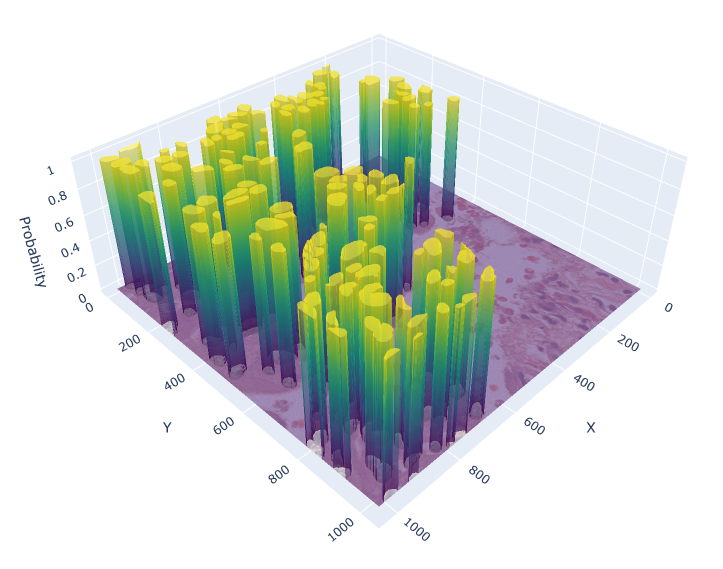

For the circle and soft IS ground truth formats we extract cell detection candidates from the segmentation prediction by applying skimage.feature.peak_local_max on the blurred foreground prediction (Figure 3), where:

Appendix 0.C Ablation study: Different values for soft IS ground truth

The value for soft IS was originally chosen based on a visual review. To investigate, whether there would be a more suitable value, we conducted an ablation study with , analyzing the performance of the soft IS model. Figure 7 shows an example of the soft IS mask for all considered values. The internal train and validation set were used for training and evaluation. The highest mean F1-Score is achieved for , while our initial choice shows a slightly lower performance by -0.6%. Notably, the choice of appears to be a compromise between precision and recall (Table 5). While lower lead to a more precise cell detection, this comes at the cost of a higher number of missed cells (false negatives). The opposite is the case for larger values. Overall, while the difference in F1-Score for and is minor, utilizing for future work is recommended.